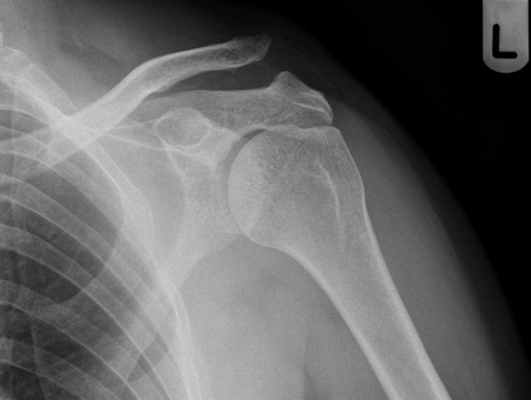

Диагноз устанавливается на основании истории заболевания, данных осмотра и рентгенологического обследования.

Появление кровоподтека в подключичной области, в области большой грудной мышцы, болезненность в этой области обычно сопутствуют разрыву ключично-клювовидных связок, то есть полному вывиху. Окончательный диагноз устанавливается при анализе рентгенограммы, которая должна выполняться в положении стоя со свободно опущенными вдоль туловища руками. Расширение ключично-клювовидного пространства при разобщении сочлененных поверхностей свидетельствуют о полном вывихе. В сомнительных случаях делают снимок здорового сустава для сравнения.

Поставить диагноз можно на основании рентгеновского снимка.

Для постановки диагноза и для определения степени повреждения акромиально-ключичного сочленения наиболее информативным методом исследования является рентген.

На рентгене при первой степени разрыва акромиально-ключичного сочленения будет видно расхождение между ключицей и акромионом.

При второй степени мы видим выступание ключицы над акромионом на расстояние не более половины ее диаметра.

При третьей степени ключица выступает над лопаткой на полный свой диаметр и даже более того.

На основании рентгена, при третьей степени повреждения, пациенту дополнительно назначается МРТ- это исследование позволит нам точно определить какие именно связки оказались разорваны, степень разрыва и поможет с выбором тактики хирургического лечения.